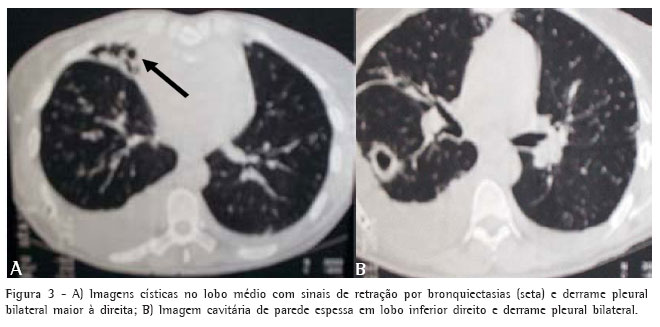

Trouxe consigo os seguintes exames: ultra-som abdominal, com leve hepatomegalia inespecífica, derrame pleural bilateral e microlitíase em vesícula biliar; e tomografia computadorizada do tórax, que apresentava derrame pleural bilateral, dilatações brônquicas císticas no lobo médio e presença de imagem cavitária no segmento apical do lobo inferior direito (Figuras 3A e 3B).

Devido ao quadro febril e de expectoração purulenta abundante em paciente com diagnóstico tomográfico de bronquiectasias do lobo médio, foi iniciado tratamento com ceftriaxona 2,0 g intravenosa a cada 24 horas e foram solicitados exames complementares, cujos resultados são descritos a seguir.